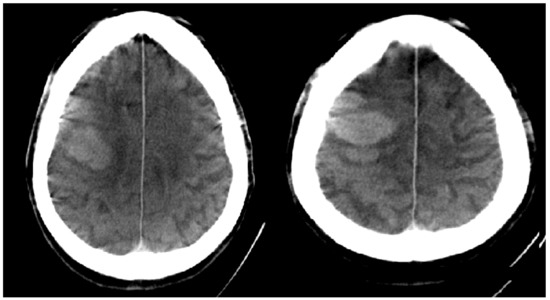

| Hemorrhage on initial FDCT | 25 (11%) | 1 (1%) | 0 (0%) | 24 (100%) | 0 (0%) | 0 (0%) |

| CT ASPECTS * | 8 (7–9) | 9 (7–10) | 0.138 |